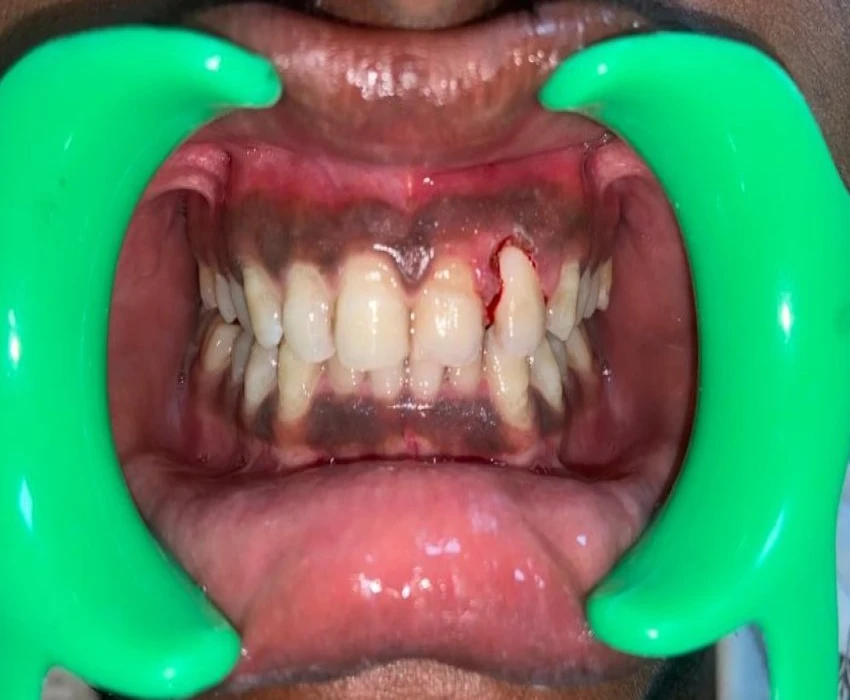

A 19 years old male patient reported to the Department of Oral Medicine and Radiology with a chief complaint of growth in left upper front region of jaw since 2 years. It was diagnosed as Pyogenic Granuloma i.r.t. 22 and differential diagnosis of Peripheral Ossifying Fibroma was given and the final diagnosis came out to be as Peripheral Cemento-ossifying Fibroma as per histopathological analysis.

Peripheral cemento-ossifying fibroma is a reactive gingival overgrowth commonly seen in anterior maxilla. It is a focal, reactive, slow-growing, non-neoplastic tumor-like growth of soft tissue, often arising from the interdental papilla. It may lead to pathologic migration and other periodontal problems.